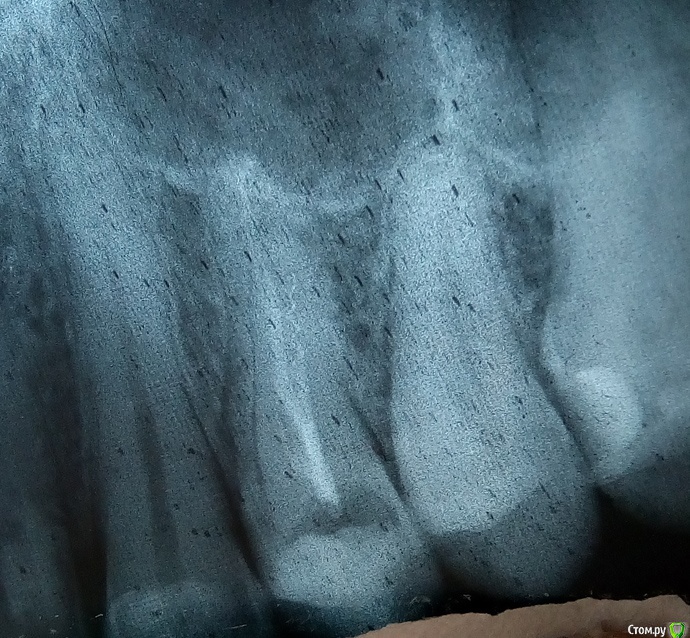

regi Опубликовано 25 февраля, 2016 Автор Поделиться Опубликовано 25 февраля, 2016 Сегодня принёс врачу снимок, она сказала что всё вроде как отлично. Я пожаловался на боль и указал на осколок на снимке, она вообще тоже заявила, что это нормально, потом отправила на повторную рентегографию на радиовизиографе. Честно говоря, на мой непрофессиональный взгляд все выглядит еще хуже, чем казалось. Прикидываю длину осколка, получается сантиметра полтора? Край очень близко к стенке корня, возможна перфорация? Врач согласилась завтра вытащить осколок, хотя я теперь реально сомневаюсь, стоит ли продолжать лечение у неё, или будет только хуже. Я так понимаю по вашим ответам, что пломбирование каналов тоже некачественное и требует переделки? Уважаемый, цели форума несколько иные, наша помощь лежит сугубо в медицинской плоскости. Прошу прощения. Я понимаю, что с этической стороны некоторые вопросы не самые приятные. Но я их задаю только потому, что хочу как раз получить надлежащую медицинскую помощь. Одно дело, если врач ошибся ненамеренно, и совсем другое, если недобросовестно подходит к своим обязанностям. Ссылка на комментарий

regi Опубликовано 26 февраля, 2016 Автор Поделиться Опубликовано 26 февраля, 2016 Железку вытащили, канал перепломбировали. Второй канал она трогать не стала, сказала, что с ним всё в порядке. Ссылка на комментарий